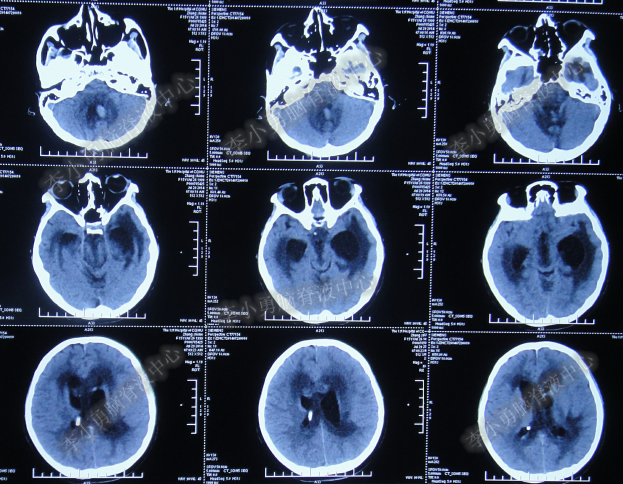

第3次手术右侧脑室外引流术后1个月时间内,脑积水仍没有得到控制,再给予腰大池引流,期间多次试图拔除右侧脑室外引流管(多次调高脑室外引流管的高度),但因患者意识变差,而无法拔除引流管,给予拔除腰大池引流,治疗期间曾多次查头部CT均示脑积水仍无改善(图-20、图-21、图-22、图-23)。

图-20:2014年7月24日头部CT

图-21:2014年7月29日头部CT

图-22:2014年8月4日头部CT

图-23:2014年8月15日头部CT